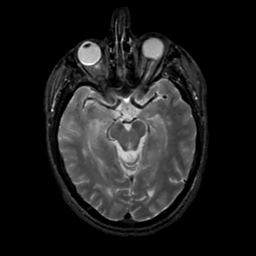

MR Study #1, February 10, 1991 -- Slice #20

[Home][Help][Clinical][Tour 1][Tour 2] Slice 20